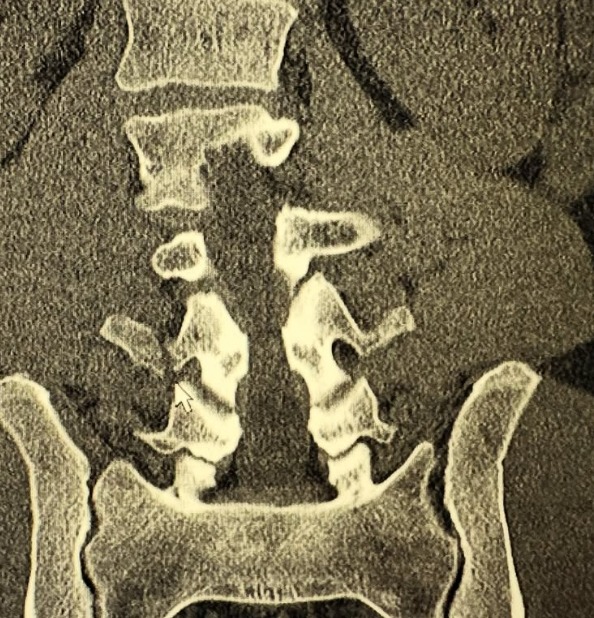

Tuesday night Sergio had a bicycle accident. He took a corner going 30 mph+, pedaled down and clipped the pavement launching him over his handlebars and flat onto his back. He broke the transverse process of L2,3,4.